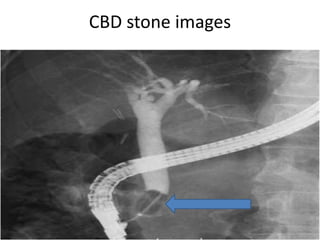

CBD stone images

Laboratory Dx & imaging

 Abdominal US (CBD sometimes not dilated)

 EUS (< 5mm stone can detected)

 MRCP

 Liver biochemical test

 ERCP- If concomitant endoscopic therapy is envisaged (high SEN)

** LFTs & Abdominal US – as initial steps (ESGE, Endoscopy,2019)